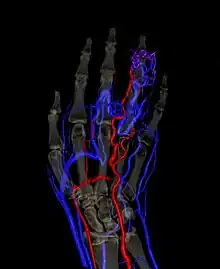

![]() | |

| a) Image with intravenous gadolinium contrast demonstrated an infiltrative vascular malformation in right gastrocnemius b) digital subtraction angiogram of right leg in a lateral projection during the arterial phase revealed arteriovenous shunting | |